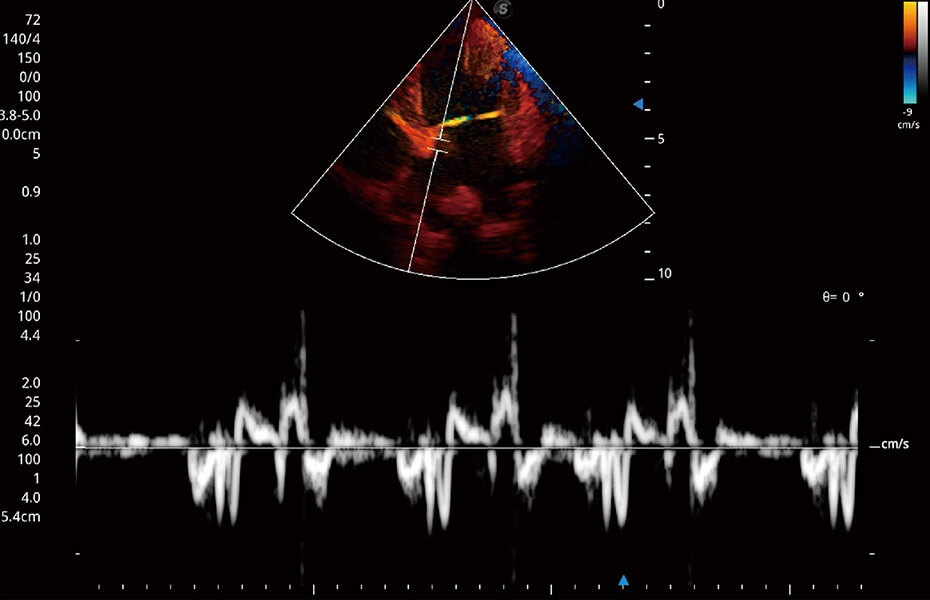

ProPet 60 作为一款高端台式动物超声设备,为动物医生的日常诊断提供了一系列贴合动物临床需求、解决临床实际问题的高级成像功能。凭借全系列高清探头,满足医生对腹部、心脏、生殖、浅表、肌骨等成像的所有需求,切实帮助您提升检查效率,提高诊断信心。

动物是人类最亲密的朋友和最值得信赖的伙伴。开立医疗也一直致力于探索动物专用的超声影像解决方案。 全新推出的ProPet系列,是开立在动物超声影像智能化、专业化、精准化的一次跨越式革新。动物不能用言语来表述自己的不适,通过超声影像,ProPet系列搭建了动物医生与不同物种沟通的“桥梁”,为动物医生注入了“治愈之力”。